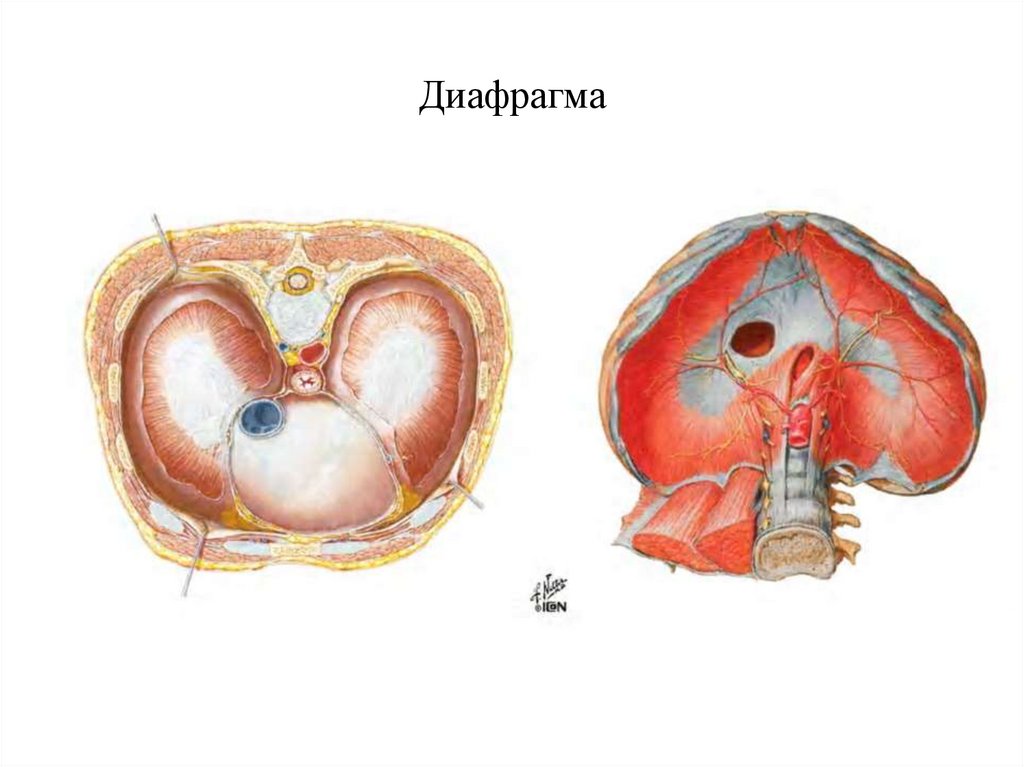

Анатомия диафрагмы и треугольника Бохдалека

Раздел: Визуальный дайджест